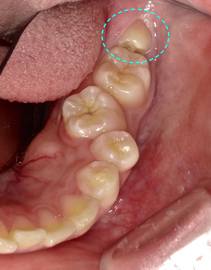

健康時とは一変、原形が分からない程大きく腫れ上がっています。ただし、見た目では親知らずの歯は確認出来ません。

レントゲンでチェックすると、横向きの親知らずの歯が存在することが確認できます。

横向きに生えている親知らずのほんの一部だけが見えています。